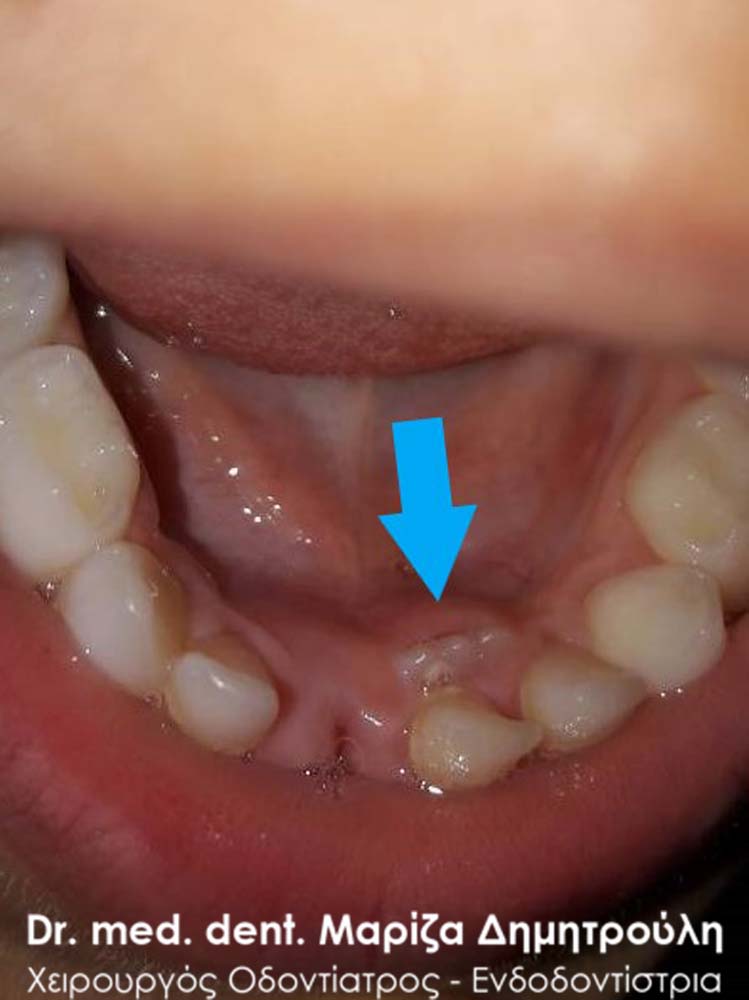

One week after the primary tooth extraction

Extraction of double primary tooth